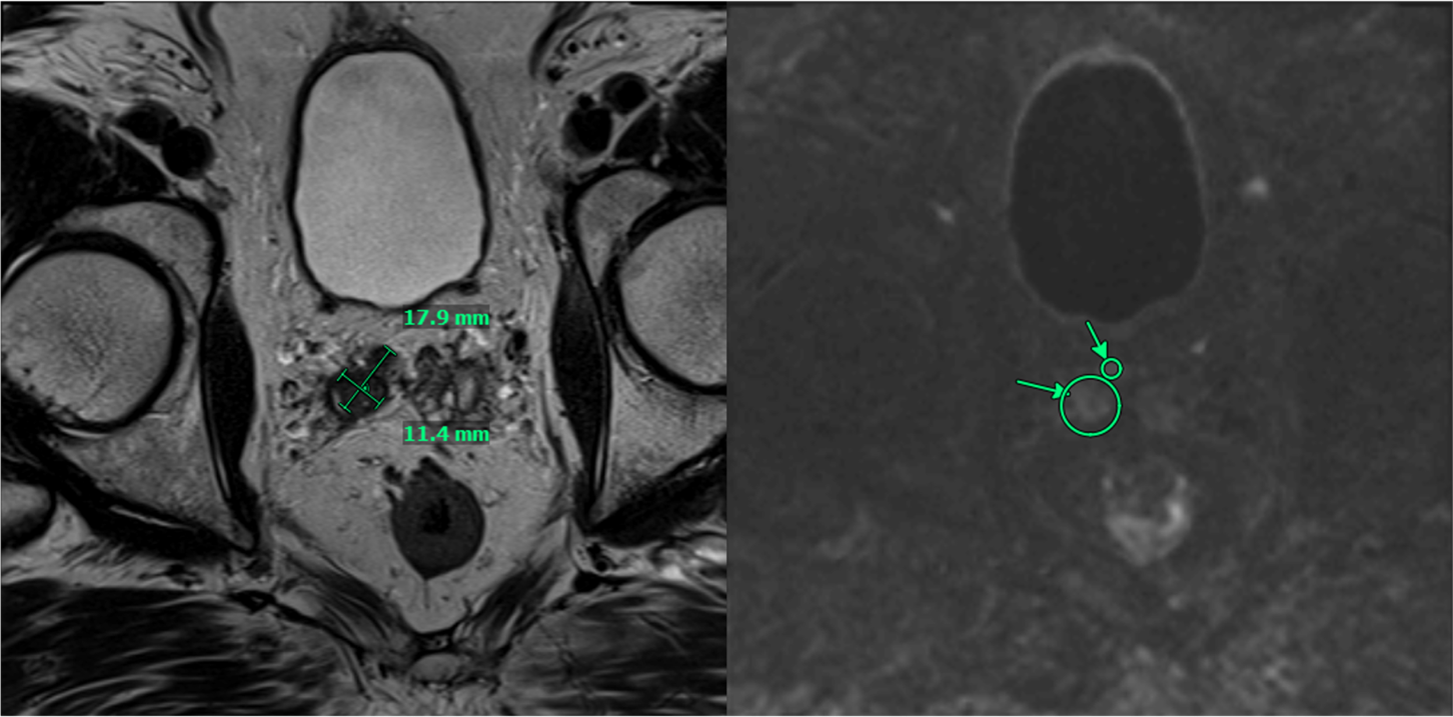

PSMA PET/CT demonstrated persistent uptake in the right posterior mid-gland and new uptake in the right SV, without nodal or distant disease (Figure 1). Multiparametric MRI (mpMRI) confirmed recurrent tumor involving the right SV and right vas deferens (Figure 2).